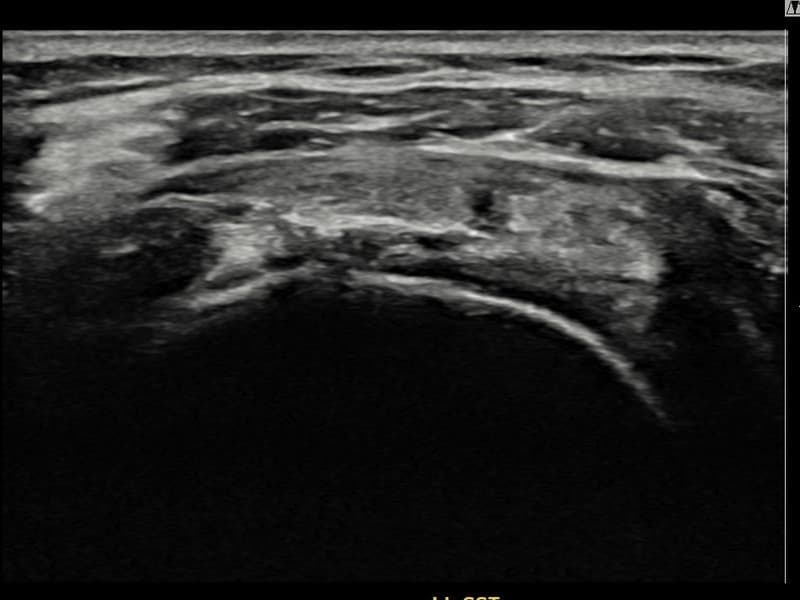

施術後

術前超音波にて左 棘上筋腱 滑液包面側部分断裂・左肩棘上筋腱のエコー不連続と腱欠損(14mm × 7mm (腱厚の約65%欠損))を確認。術後超音波では断裂部位が再生組織で充填され、腱の連続性回復とエコーパターンの正常化が確認されました。